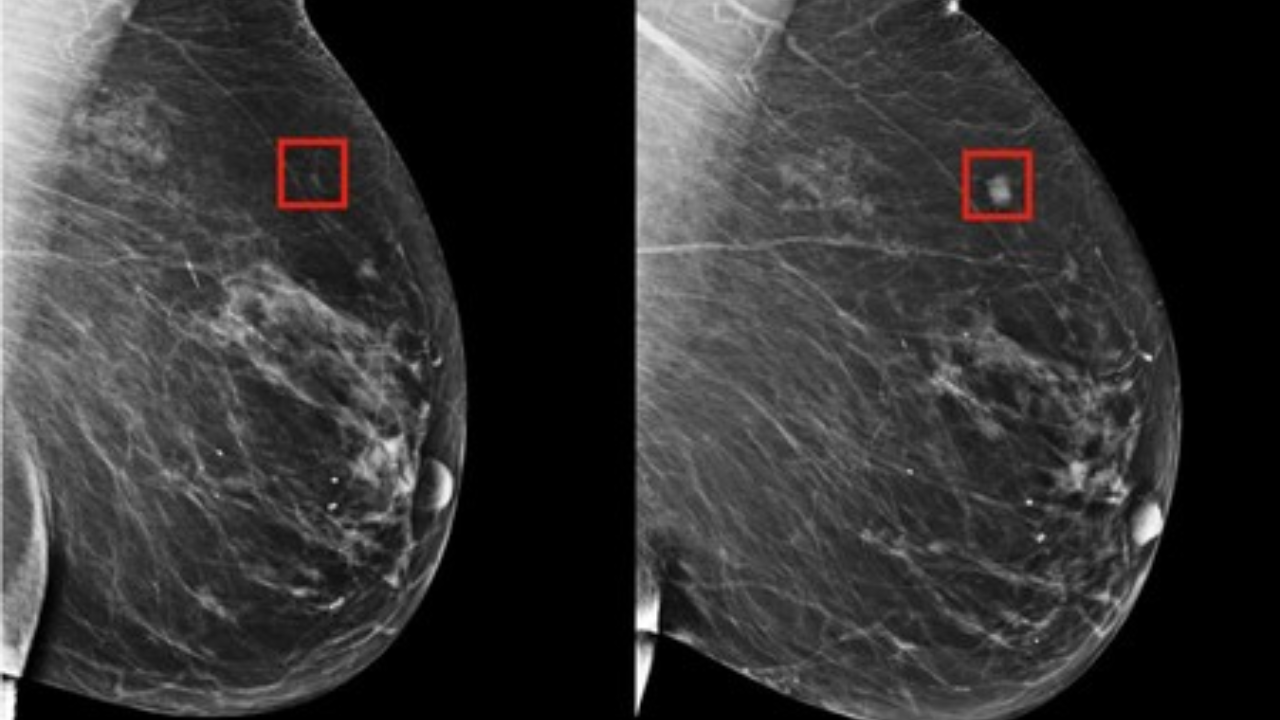

Herramienta de inteligencia artificial puede detectar el cáncer de seno en mujeres